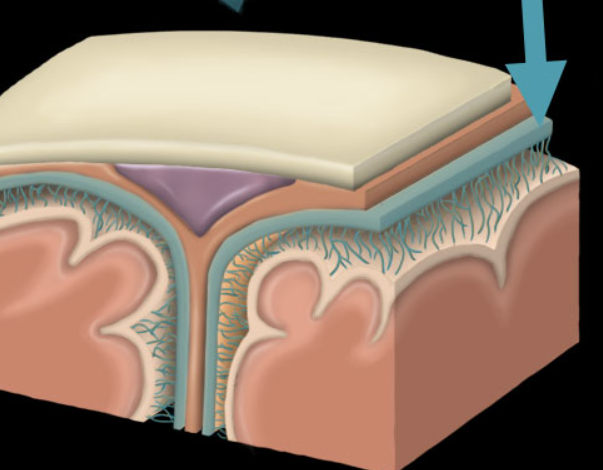

dura mater

arachnoid mater

Pia mater

dural sinus